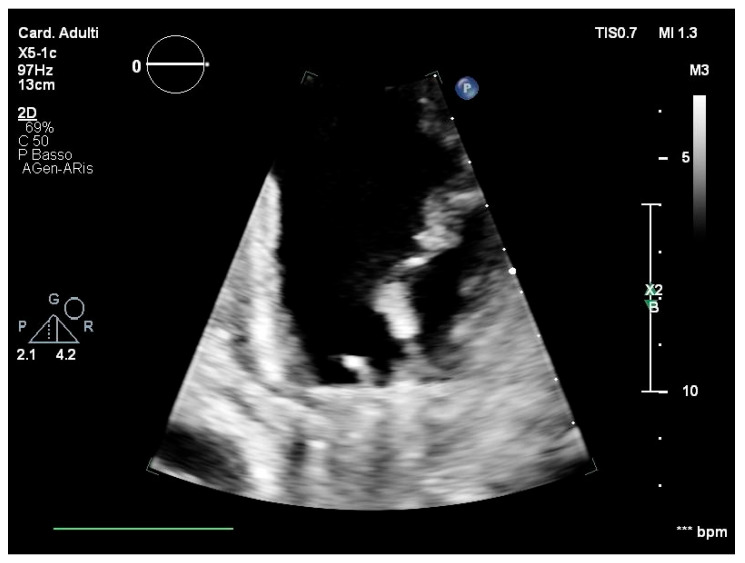

Case report: A 28-year-old male patient was referred to the cardiac surgery unit for urgent mitral valve replacement due to suspicion of infective endocarditis. Microbiological tests yielded negative results. Following recovery and discharge with antimicrobial therapy for 6 weeks, the patient experienced prosthesis detachment, necessitating re-hospitalisation for an emergency valve replacement. Vibrio metschnikovii was identified on the prosthesis valve through PCR and successfully treated with ciprofloxacin. However, a spontaneous rupture of the ascending thoracic aorta led to a neurological injury.